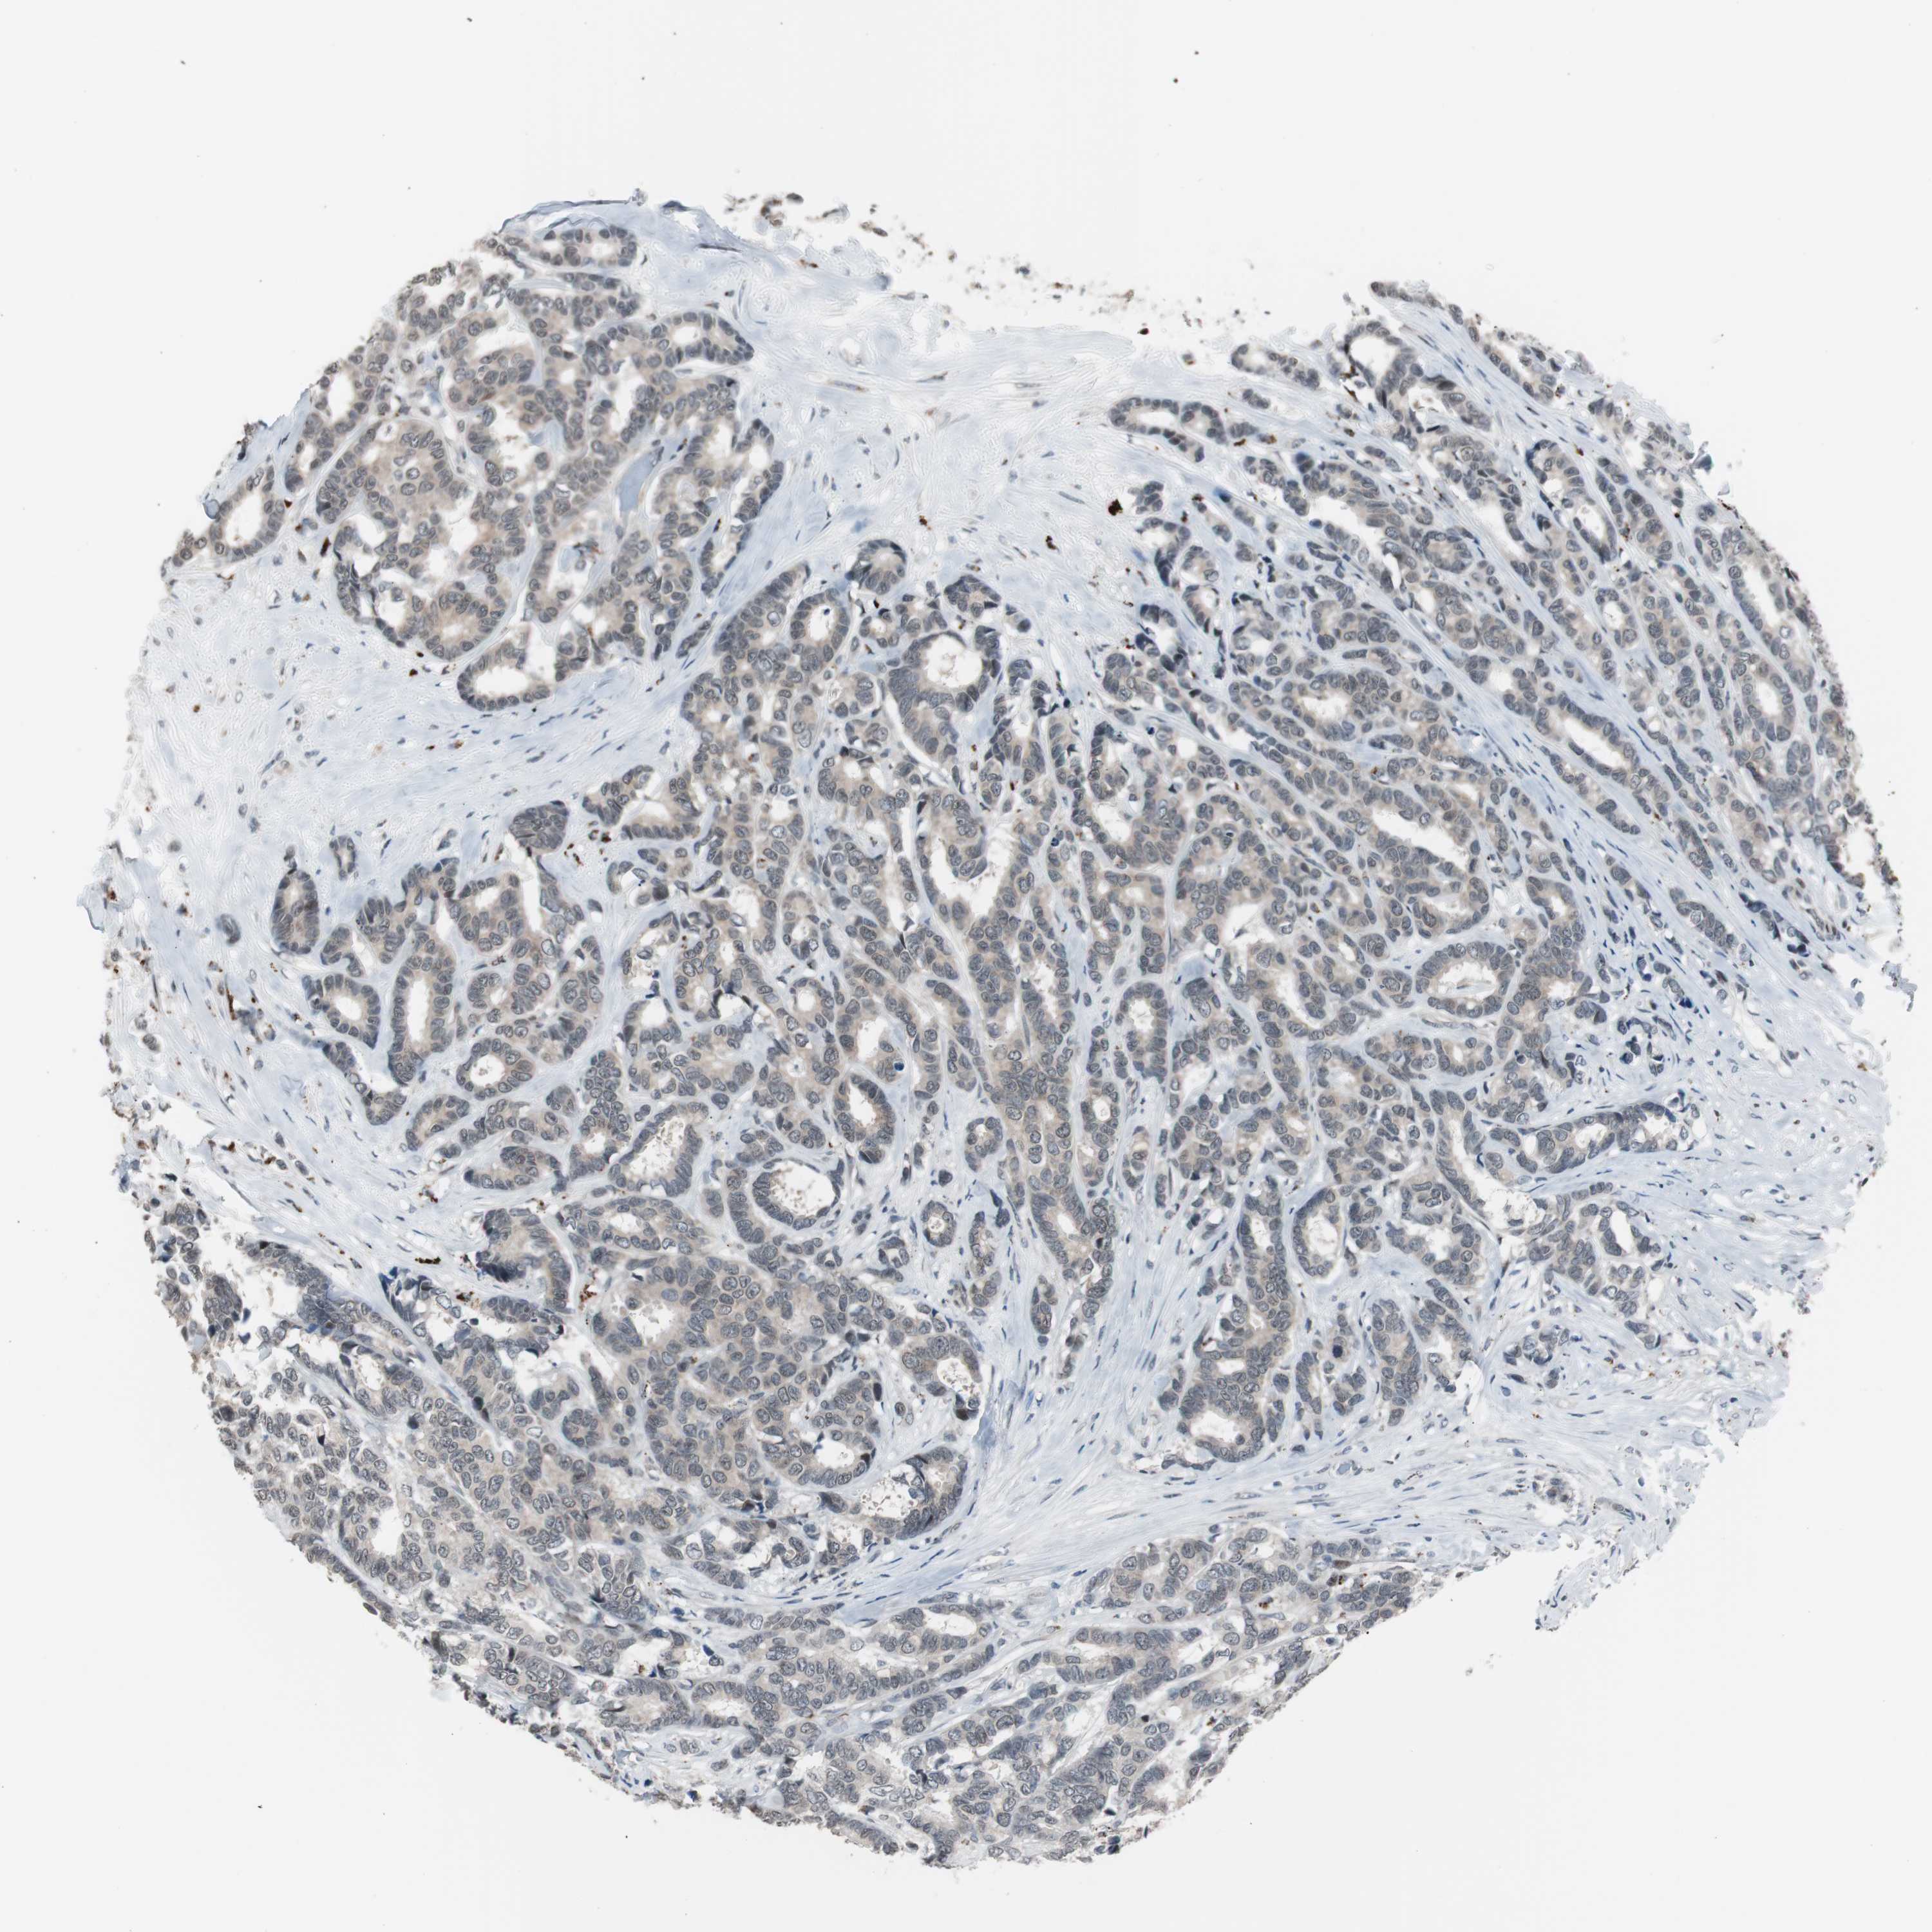

CANCER BREAST CANCER Show tissue menu

BRCA TCGA BRCA VALIDATION PROTEIN EXPRESSION

Breast cancer

Human cancer

Breast invasive carcinoma